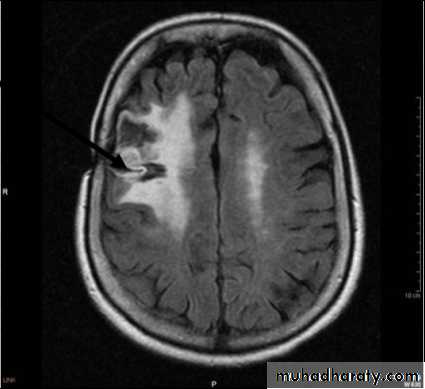

• Computed Tomography scan (CT scan) with/without contrast• Magnetic Resonance Imaging (MRI) with/without contrast